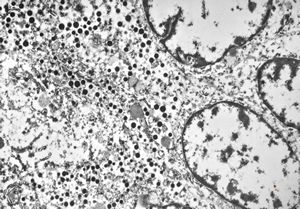

F, 71y. | carcinoid … metastasis to lymphonode